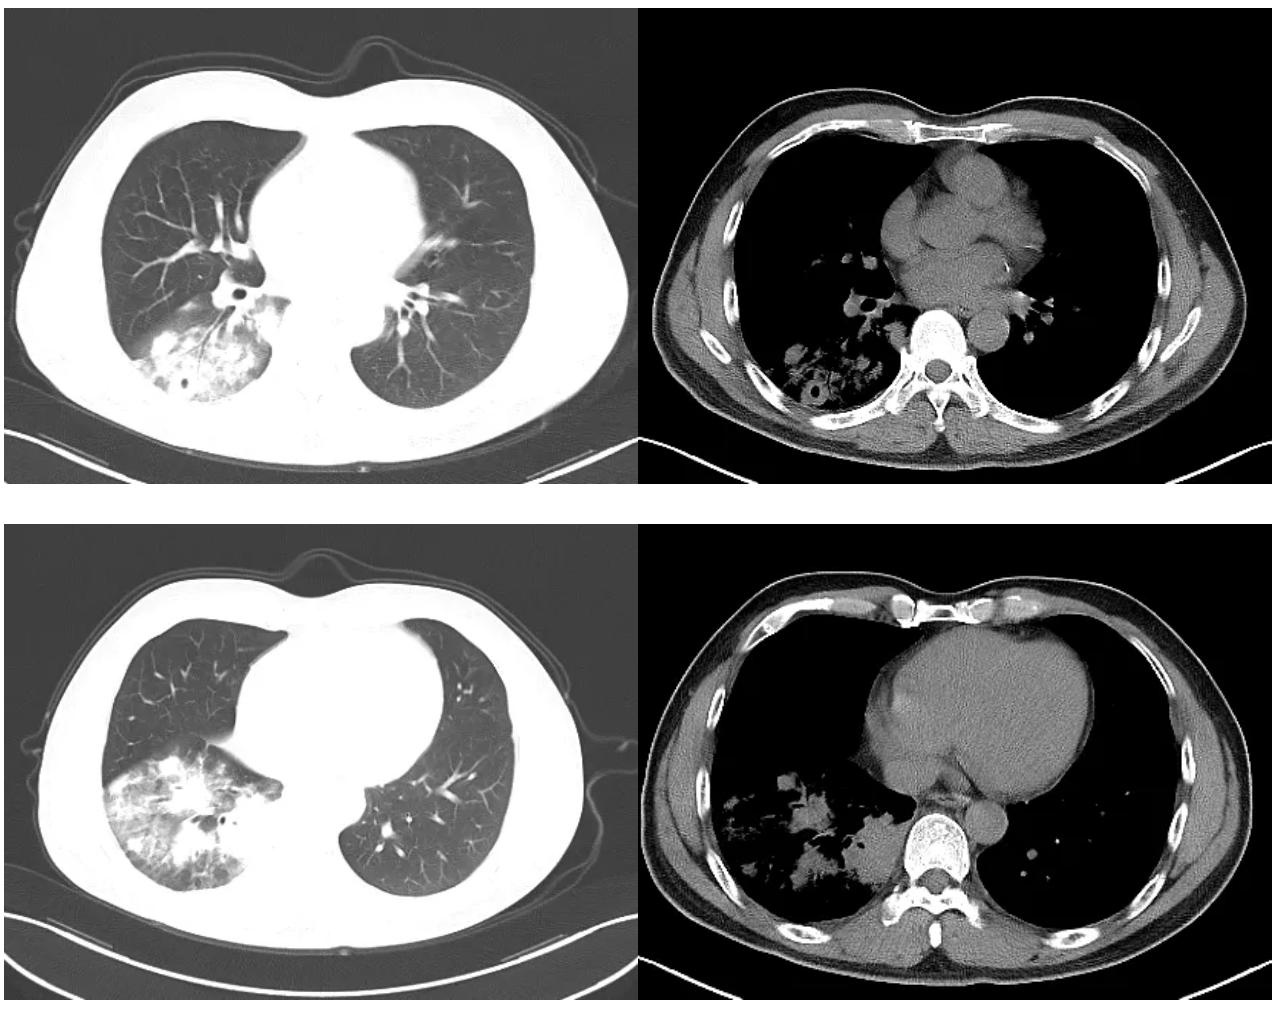

抗感染治疗7天后,患者未再出现痰中带血,但咳嗽、胸闷症状无明显缓解。 复查胸部CT较院外旧片比进展 (图2)。

图2:胸部CT示右下肺炎症,可见空洞形成。

综合分析原因有两种可能性,一是抗生素未覆盖致病菌,二是非细菌感染或者非感染性疾病所致。但考虑患者生命体征平稳,未升级抗生素,而是进一步寻找病因:完善纤维支气管镜检查,镜下见气管及各级支气管粘膜光滑,管腔通畅,可见少量粘稠分泌物,抽取分泌物送细菌培养,并0.9%生理盐水灌洗右下叶背段支气管,留取灌洗液送检真菌GM试验、抗酸染色、弱抗酸染色、真菌涂片及病原学mNGS,于7组淋巴结行EBUS-TBNA,于右下叶后基底段支气管行EBUS-TBLB。结果回示真菌GM试验、抗酸染色、弱抗酸染色、真菌涂片均阴性;7组淋巴结穿刺细胞块病理回示渗出背景上少量淋巴细胞,右下叶TBLB肺活检示肉芽肿性炎(图3),抗酸染色(-),PAS(-),六胺银(-),TB-DNA(-)。